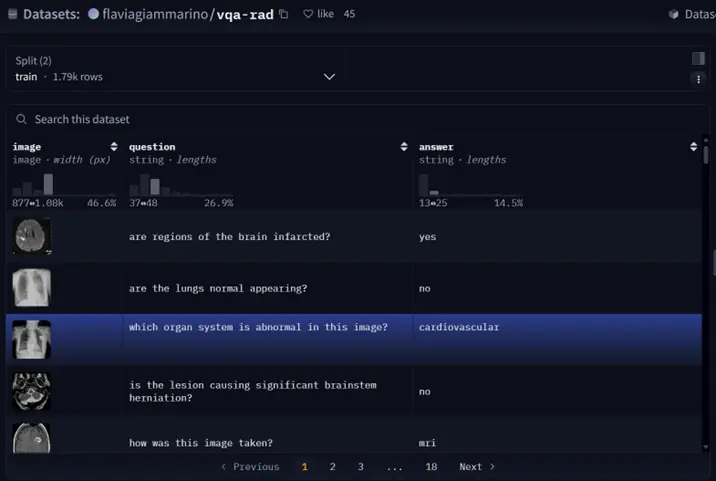

數據簡介

VQA-RAD 是一個關於放射影像的問題-答案對數據集。

- 數據集用途

訓練和測試醫學影像VQA(視覺問答)系統

支持開放式問題(如“病灶位置?”)和二元問題(如“是否存在腫瘤?”)

- 數據來源

基於MedPix(開放醫學影像數據庫)

由臨牀醫生手動標註,確保專業性

- 核心優勢

首個專注放射影像的VQA數據集

結構清晰,覆蓋臨牀常見問題類型

數據處理

- 數據獲取

from datasets import load_dataset

dataset = load_dataset("flaviagiammarino/vqa-rad")- 處理前